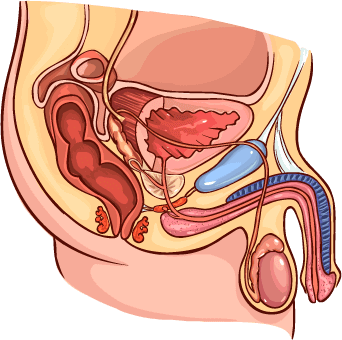

Recuperar de forma segura la erección y la potencia

(contribuye a la producción de testosterona, aumenta la libido, mejora la erección)